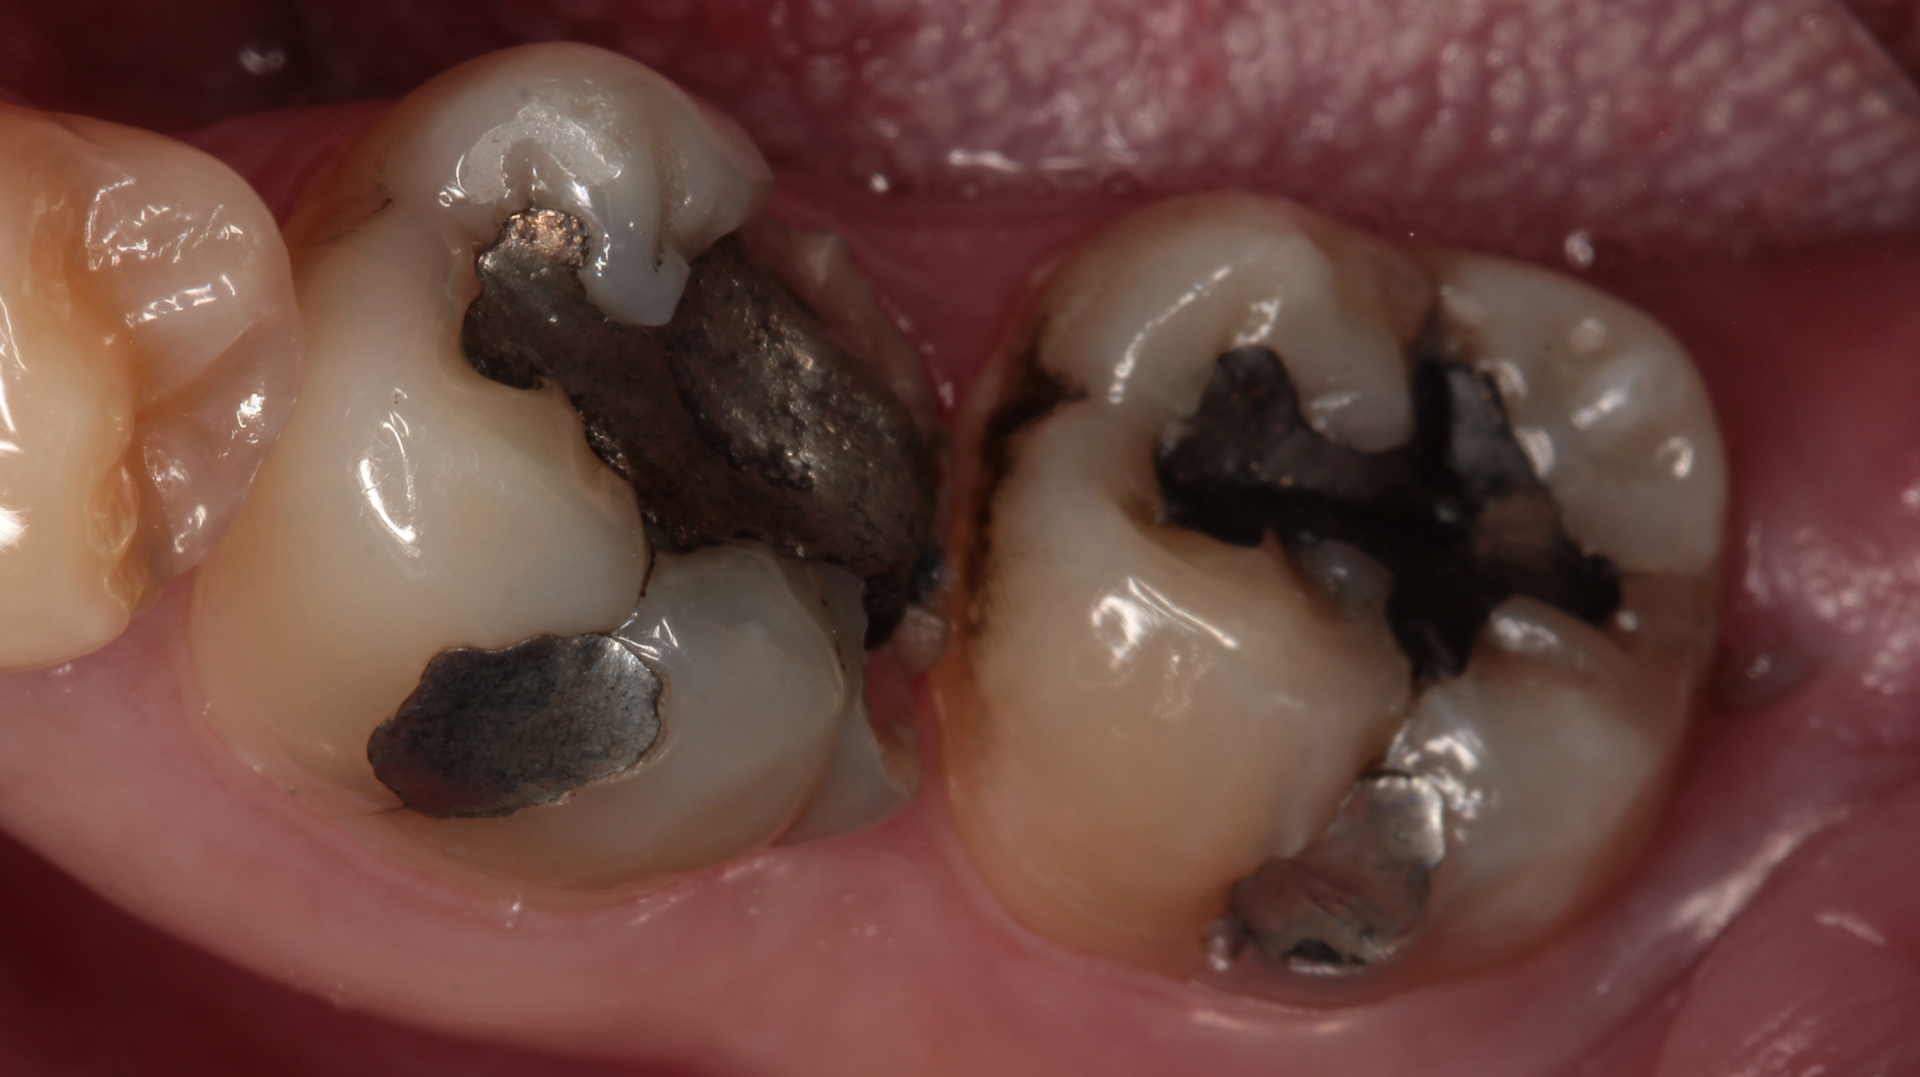

Case presentation

A patient presents with large cavities that have been previously addressed with amalgam. After removing the amalgam and achieving isolation, an alginate is used to take an impression (figures 1–4). A working model is made by first placing light silicone material in the impression and then supporting it with putty to provide rigidity (figures 5a-c). A second working model is made to allow for “flexion” of the dies. This allows separation of the individual teeth and preparations for adjusting proximal margins and interproximal contacts of the restoration as needed.